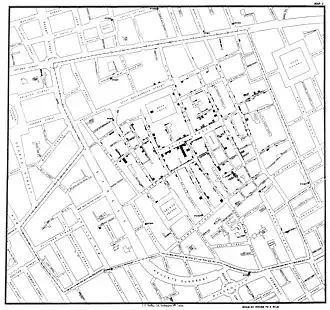

General images –